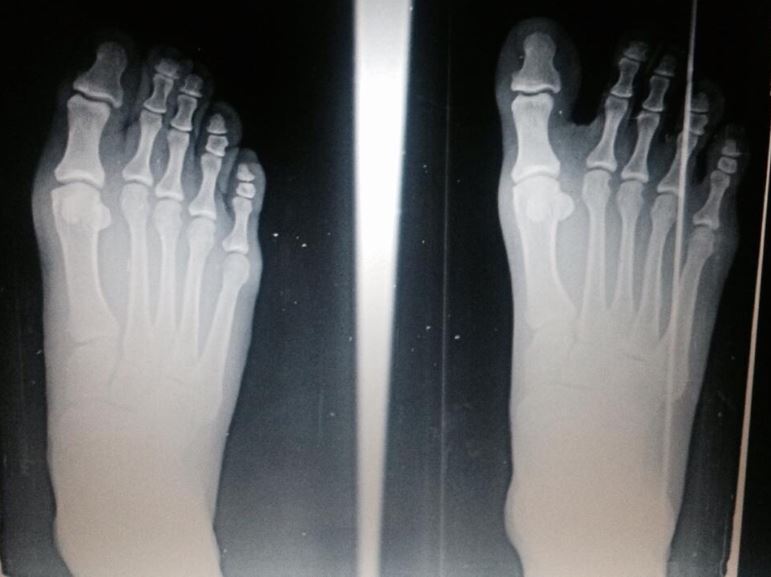

En este primer ejemplo se puede apreciar mediante radiografías estos cambios tras dos años de un adecuado uso de este calzado (articulo). La mejora en la alineación de los dedos es impresionante y uno de los grandes problemas a largo plazo en corredores.

En un segundo articulo podemos ver cambios más profundos con un ejemplo real de un paciente con pies planos, un marcado valgo de tobillo y rodilla que implicaban dolor en rodillas y espalda baja a pesar de utilizar plantillas individualizadas. El protocolo del doctor fue eliminar de manera gradual las plantillas durante los entrenamientos (realizando la primera parte sin plantillas y la final con ellas). A continuación, comienzo de uso de calzado minimalista sin superar en ningún momento el 10% de incremento de kms semanales y siempre comenzando el entrenamiento con este calzado y pasando después al convencional.

Según el Dr. Campitelli el calzado minimalista es una herramienta ideal para fortalecer y realizar una reconducción postural como puede verse en estas imágenes.